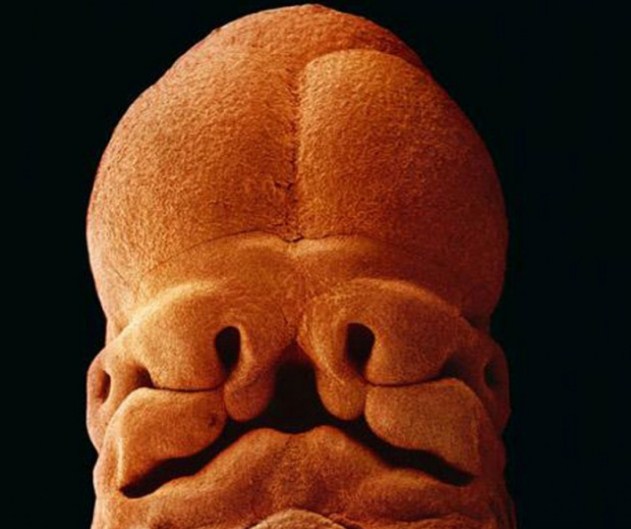

На 5 седмици зародишът е дълъг 9 милиметра; вече е възможно да се види лицето с отворите за уста, ноздри и очи.

40 дни от развитието. Външните клетки на зародиша се свързват с повърхността на матката, за да образуват плацентата.

8 седмици от развитието.